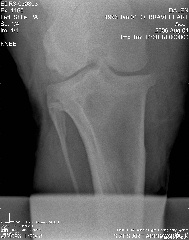

Here are the xrays from today:

Stifle oblique:

Stifle Oblique

Hi Dr. O, after reading your article, I've added the lateral view of the stifle, can you tell if you can see if he has any of the following?

osteochonDrOsis dissecans

subchondral bone cyst

osteoarthritis

Stifle Lateral view

stifle lateral

Aileen, carefully reviewing an extensive list of radiographs like you have above for any abnormality even with the original set of full sized radiographs could take up to an hour and an hour more to write about. Reviewing these tiny pictures would be of no value at all. While I don't mind looking at the occasional radiograph the above is beyond the scope of this site.

If you want a second opinion on these I strongly recommend you send them to a certified veterinary radiologist, like you find at a university veterinary school, they could tell you more than I would be able to.

Surgeon says mild to moderate djd in hocks and stifle. His stiffness is much much better, not overall anymore, so I do think the hock injections helped.